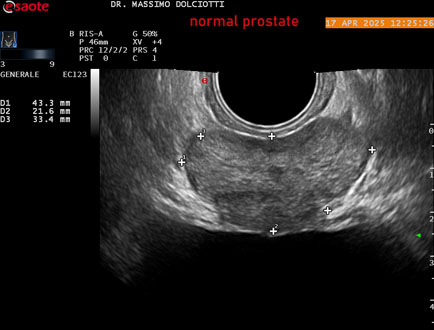

Data inserimento: 01/10/2025

Ecografia del: 17/04/2025

Strumento: Esaote MyLab Eight

Sonda: Convex Multifrequenza 1-8 MHz, Endocavitaria Multifrequenza 3-9 MHz e 3-13 MHz

Età Paziente: M 35 anni

Motivazione dell'esame: disuria.

Commento all'esame: le immagini ed il video documentano la prostata di ecostruttura regolare e morfovolumetria normale con diametro trasversale di 40 mm, diametro anteroposteriore di 21 mm e diametro longitudinale di 43 mm, con volume prostatico calcolato di 18 cc (v.n. < 20 cc), il profilo prostatico è regolare e netto, non si documentano calcificazioni intraghiandolari, la vascolarizzazione della ghiandola è normale. La vescicola seminale destra presenta diametro longitudinale di 44,4 x 7,8 mm, la vescicale seminale sinistra ha diametro longitudinale di 45,3 mm x 7,2 mm.

Conclusioni: prostata normale (normal prostate).